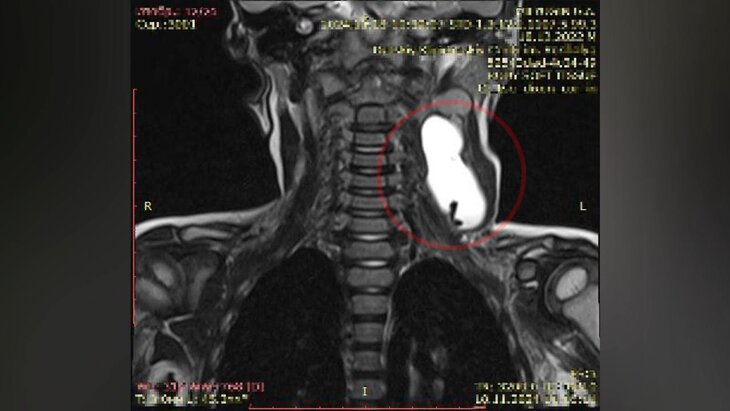

Ребенок поступил в медцентр с асимметрией лица и шеи. В ходе обследования у него выявили доброкачественную опухоль, при которой сдавливается яремная вена и сонная артерия. Из-за этого у мальчика нарушился отток лимфы в области головы и шеи.